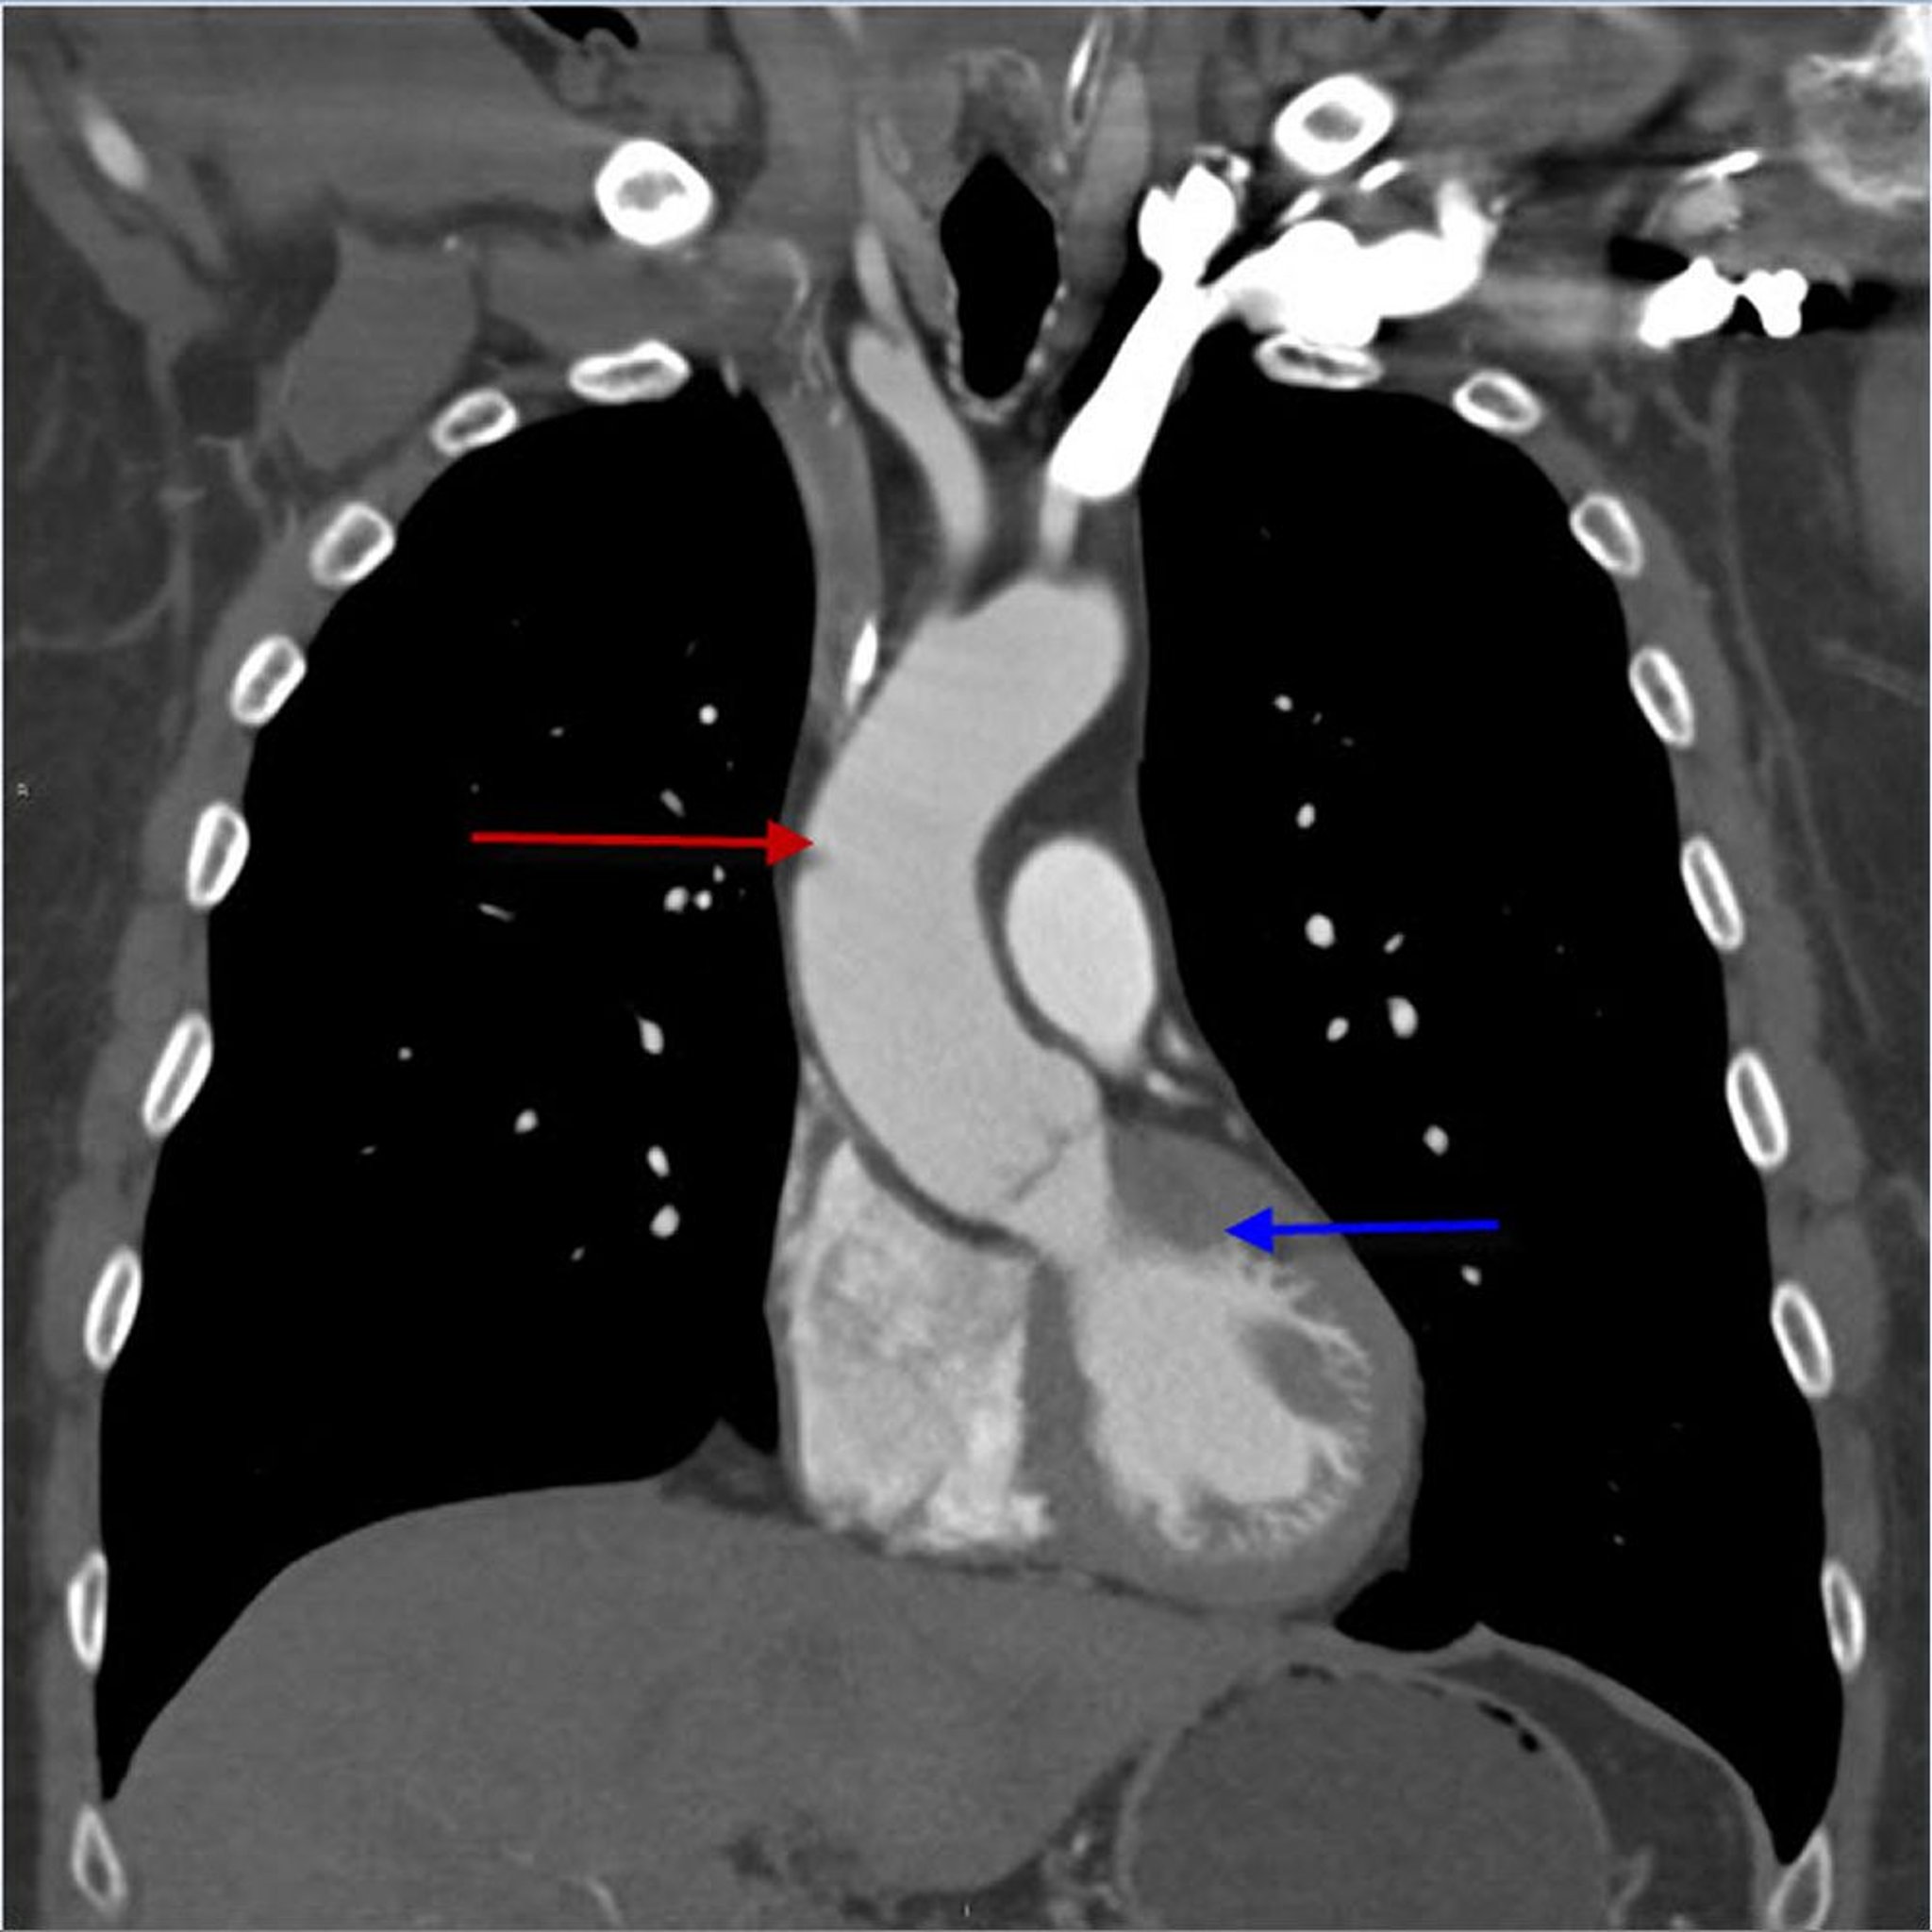

Angio-TDM (vue coronale) du thorax montrant l'aorte thoracique ascendante

Cette image montre l'aorte thoracique ascendante (flèche rouge) provenant du ventricule gauche (flèche bleue).